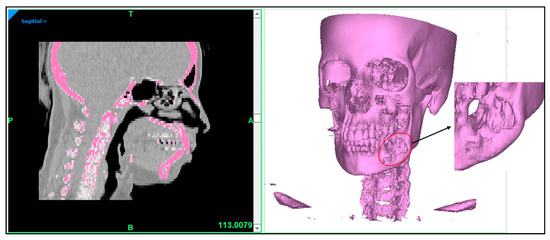

2.2. Image Acquisition and Processing